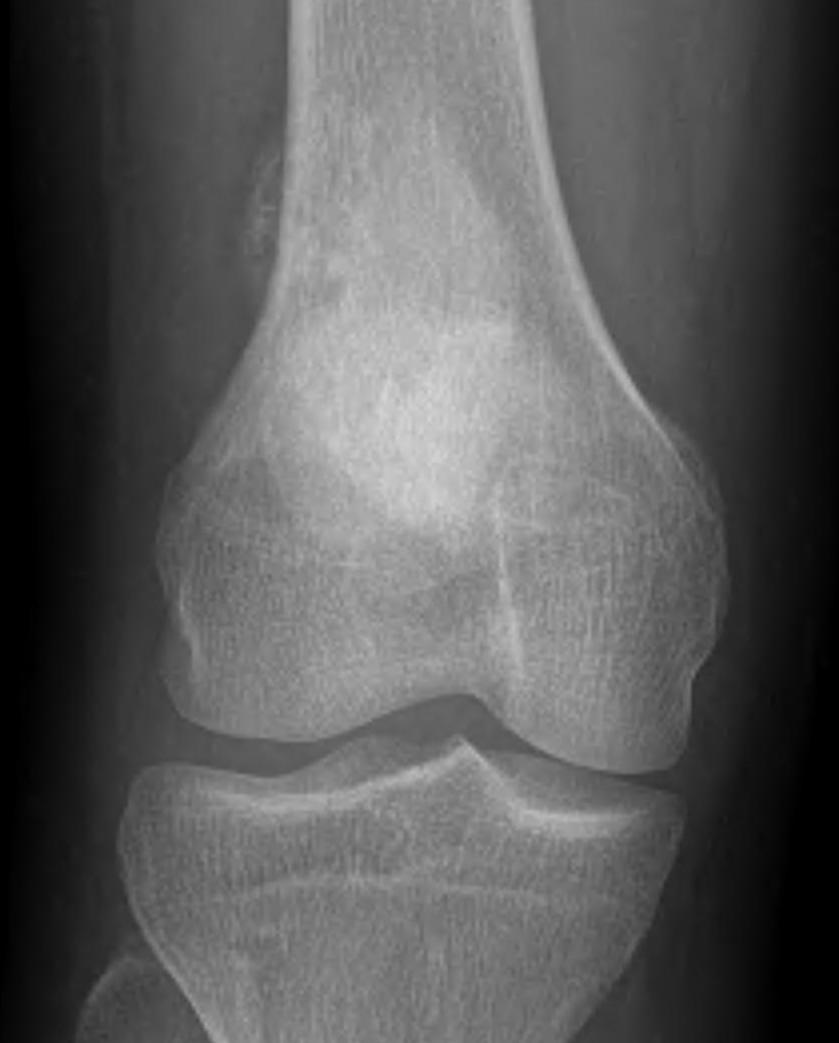

X-ray

May look like osteochondroma

- large lobulated broad-based lesion

- mature bone arising from cortex

- underlying cortex may be thickened

- 25% invade periosteum

"String Sign"

- wraps around bone with intervening periosteum

- well-defined radiolucent line between lesion & cortex

Parosteal osteosarcoma distal femur